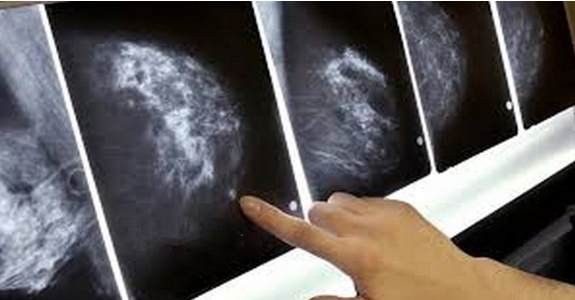

A few years ago they “diagnosed” my close friend with ductal carcinoma in situ (DCIS), conveniently labeled an early form of breast cancer.

Oncologists often lie to their patients about the diagnosis